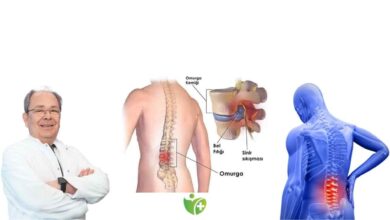

Kas ve kemik arasında ilerleyen sinirler, beyinden aldığı sinyalleri vücuttaki organlara taşıyan kablo benzeri yapılardır. Sinirler, deriden aldıkları dokunma, soğuk, sıcak gibi duyuları da üst merkezlere iletmekle görevlidir. Sinir sıkışması, insan vücudundaki tendon, kemik ve kıkırdak gibi dokuların sinirlere baskı yapması sonucundan ortaya çıkmaktadır. Sinir sıkışmalarına tuzak nöropati denilmektedir. Tuzak nöropatilerin % 90’nını elde meydana gelen ‘karpal tünel sendromu’ oluşturmaktadır. Geçirilen travmalar, ameliyatlar, kırık iyileşmesi sürecinde ortaya çıkan aşırı gelişmiş bağ dokuları da sinir sıkışmasına neden olabilmektedir. Ayrıca fıtıklar, kemik çıkıntıları ve omurilik kanalındaki daralma da sinir sıkışmasına yol açabilmektedir.

Sinirler neden sıkışır?

Dokuların sinirlere uyguladığı baskı sonucunda ortaya çıkan sinir sıkışmasının nedenleri çok fazladır. Sinir sıkışmasının nedenleri arasında aşağıdakiler olabilmektedir.

- Bel fıtığı sinir sıkışmasının önemli bir nedenidir.

- Omurga üzerindeki omurlar arasındaki jölemsi maddenin dış tabakasının yırtılmasıyla ortaya çıkan disk fıtıklaşması sinirleri ve sinir köklerini sıkıştırabilmektedir.

Sinir sıkışmasının 4 türü

Sinir sıkışmasının bilinen önemli çeşitleri şunlardır:

- Karpal tünel sendromu (el bileğinde sinir sıkışması)

- Fıtıklaşmış disk (omurga üzerinde sinir ve sinir kökü sıkışması)

- Kubital tünel sendromu (dirsekte ulnar sinir sıkışması)

- Peroneal sinir sıkışması (bacakta ve dizde sinir sıkışması)